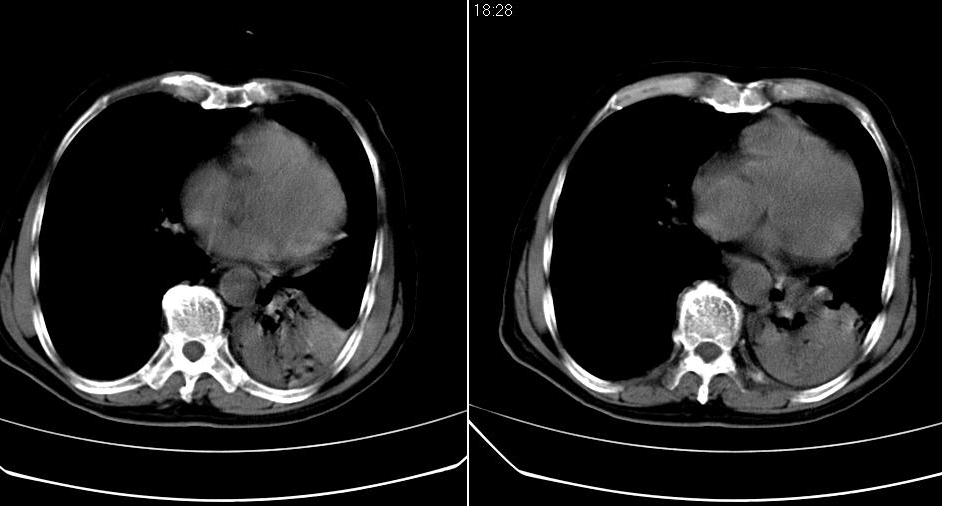

男 80岁,外院病人,有脑梗塞病史,近两个月发热,体温38.5度左右,抗炎后体温正常,药物停有发热。

左肺下叶略萎陷、实变,内可见含气支气管征。左舌叶、中叶亦见少许斑片状高密度区,边界不清。纵隔未见肿大淋巴结影。

左下肺体积缩小,密度增高,见片增密影。边界模糊,见支气管充气像,肺门纵隔无异示,心脏气管左移,左侧胸腔少量积液。考虑肺部感染伴部分肺不张[有脑梗塞病史坠积性肺炎可能]

左下肺体积缩小,密度增高,并见大片状致密影,边界模糊,其内见支气管充气像,肺门纵隔无异常,心脏气管左移,左侧胸腔少量积液。考虑:左肺炎性病变伴不张。